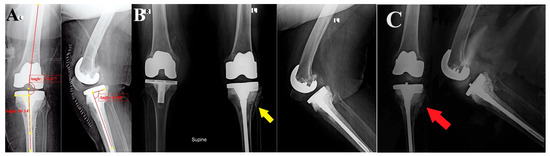

Various management options were described to manage tibial PPFs after TKA (Figure 4), including non-operative methods (cast or brace), fracture fixation (using plates and screws or intramedullary nails or external fixators), revision TKA (single component or whole revision), and up to knee arthrodesis or amputation (if any other solution failed). These options rely mainly on the location of the fracture (type Ⅰ, Ⅱ, Ⅲ, and Ⅳ), the stability of the tibial component (subtype A or B), and the time of occurrence (subtype C, referring mainly to an intraoperative fracture) [11,15,18,21].

Figure 4. Various management options are based on the classification of Felix et al. [15].